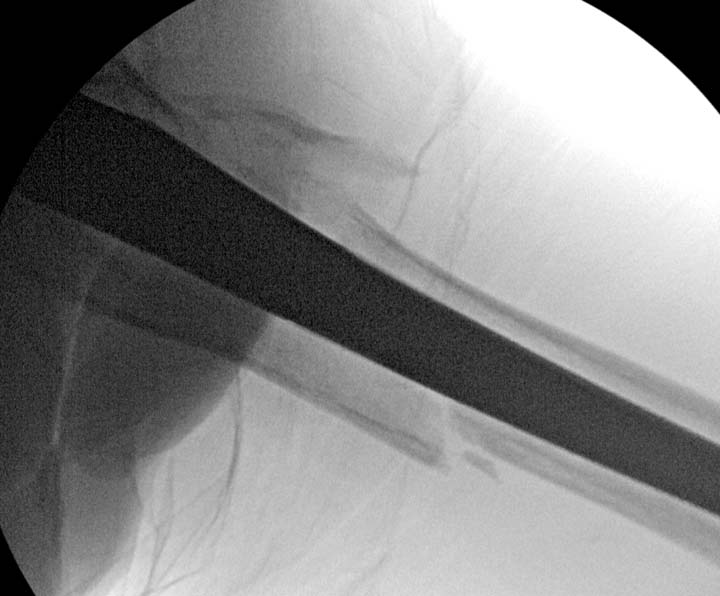

Операция не обошлась без казуса, при подготовке гвоздя произошла ошибка

в расчете. Пришлось коррегигировать по ходу операции, где длинный

дистальный отдел гвоздя срезали во время операции.